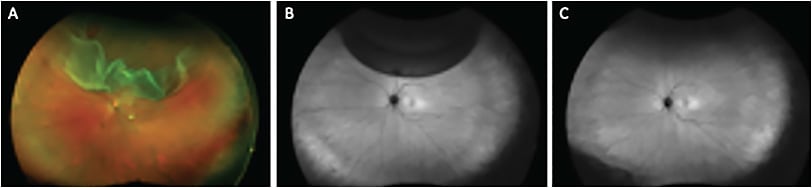

In minimal gas vitrectomy (MGV), air fluid exchange is completely avoided and a small expansile bubble of 0.6cc of pure SF6 gas is injected at the completion of surgery.3

The patient positions similar to how they would for PnR, and the retina reattaches naturally by the action of the RPE pump. This is likely to lead to a better integrity of reattachment compared with standard PPV with a full gas fill in terms of retinal displacement (LIRA/HIRA) (Figure 2).